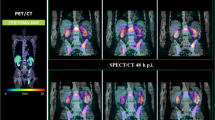

The first step was to identify isotoxic dose resulting in liver damage for treatment using different schedules and techniques. We exploited the concept of SRT-induced area of liver damage called focal liver reaction (FLR). FLR refers to the change in imaging features of the liver parenchyma adjacent to the SRT target lesion, corresponding pathologically to veno-occlusive disease. [24] We hypothesize that such damage becomes evident at MRI for similar biologically effective doses (BED), despite the dose-fractionation used. We exploited the unique features of FLR imaging to identify BED values needed to induce FLR. We delineated on each available 3 months follow-up MRI of each patient (on hepatobiliary phase, fat suppressed T1 weighted images) the FLR. Original plans and original DICOM images of planning CT were coregistered with the corresponding follow-up MRI. Two trained radiation oncologist delineated area of FLR on each available MRI image, after the delineation a radiologist with more than 10 years of experience on liver MRI supervised and confirmed the results. To identify best fitting isodose corresponding to FLR, Conformity Index (CI) was assessed for each patient on each RT plan available and was defined as follows:

where “A” consists in isodose overlapping with liver and “B” the FLR. The contouring was performed on the Velocity™ software both for photons and protons treatments. A representation of the process is reported in Fig. 1. Mean CI and mean isodose related to FLR were computed for patients treated with schedules of three, five and fifteen fractions, with the objective to identifying mean isotoxic doses.

Representation of the isodose extraction process. In brief, coregistration of planning CT and 3 months follow-up MRI (hepatobiliary phase, fat-suppressed T1 weighted images), delineation on the FLR on MRI, coregistration of dose deliverd and CI extraction. Such process has been performed for all patients respecting study inclusion criteria